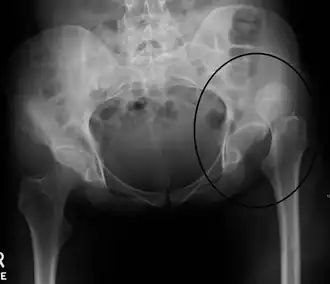

| Radiografia em que se observa deslocação da articulação na anca esquerda | |